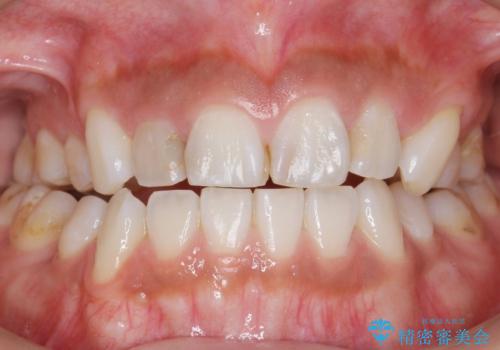

フロスを通すと臭い 歯と歯の間の虫歯 セラミックインレー 30代女性

- 歯と歯の間の虫歯治療を希望された患者様です。

フロスを通すと臭いのが気になるとの事でした。

精査したところ、左上の奥歯の間(左上56間)にう蝕を認めました。

う蝕を丁寧に除去したのち、セラミックインレーによる修復を行いました。